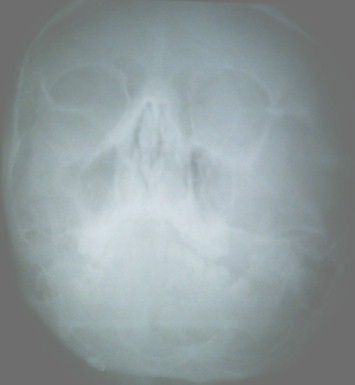

Radiografía de senos perinasales.

Conclusión:

Síndrome de malposición cardiaca. Dextrocardia con situs inversus sin asociación de otras malformaciones cardiacas. Se tuvo en cuenta el cuadro clínico sugestivo de una sinusitis aguda la que no se comprobó posteriormente con la radiografía de senos perinasales porque se aplicaron antibióticos antes de efectuarla.